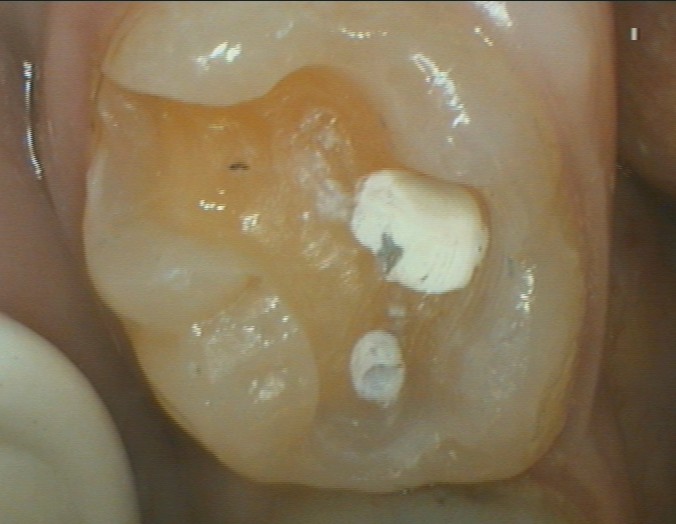

Die defekte Füllung und Karies wurde aus dem Zahn entfernt. Es wurde nur soviel, wie nötig am Zahn beschliffen.